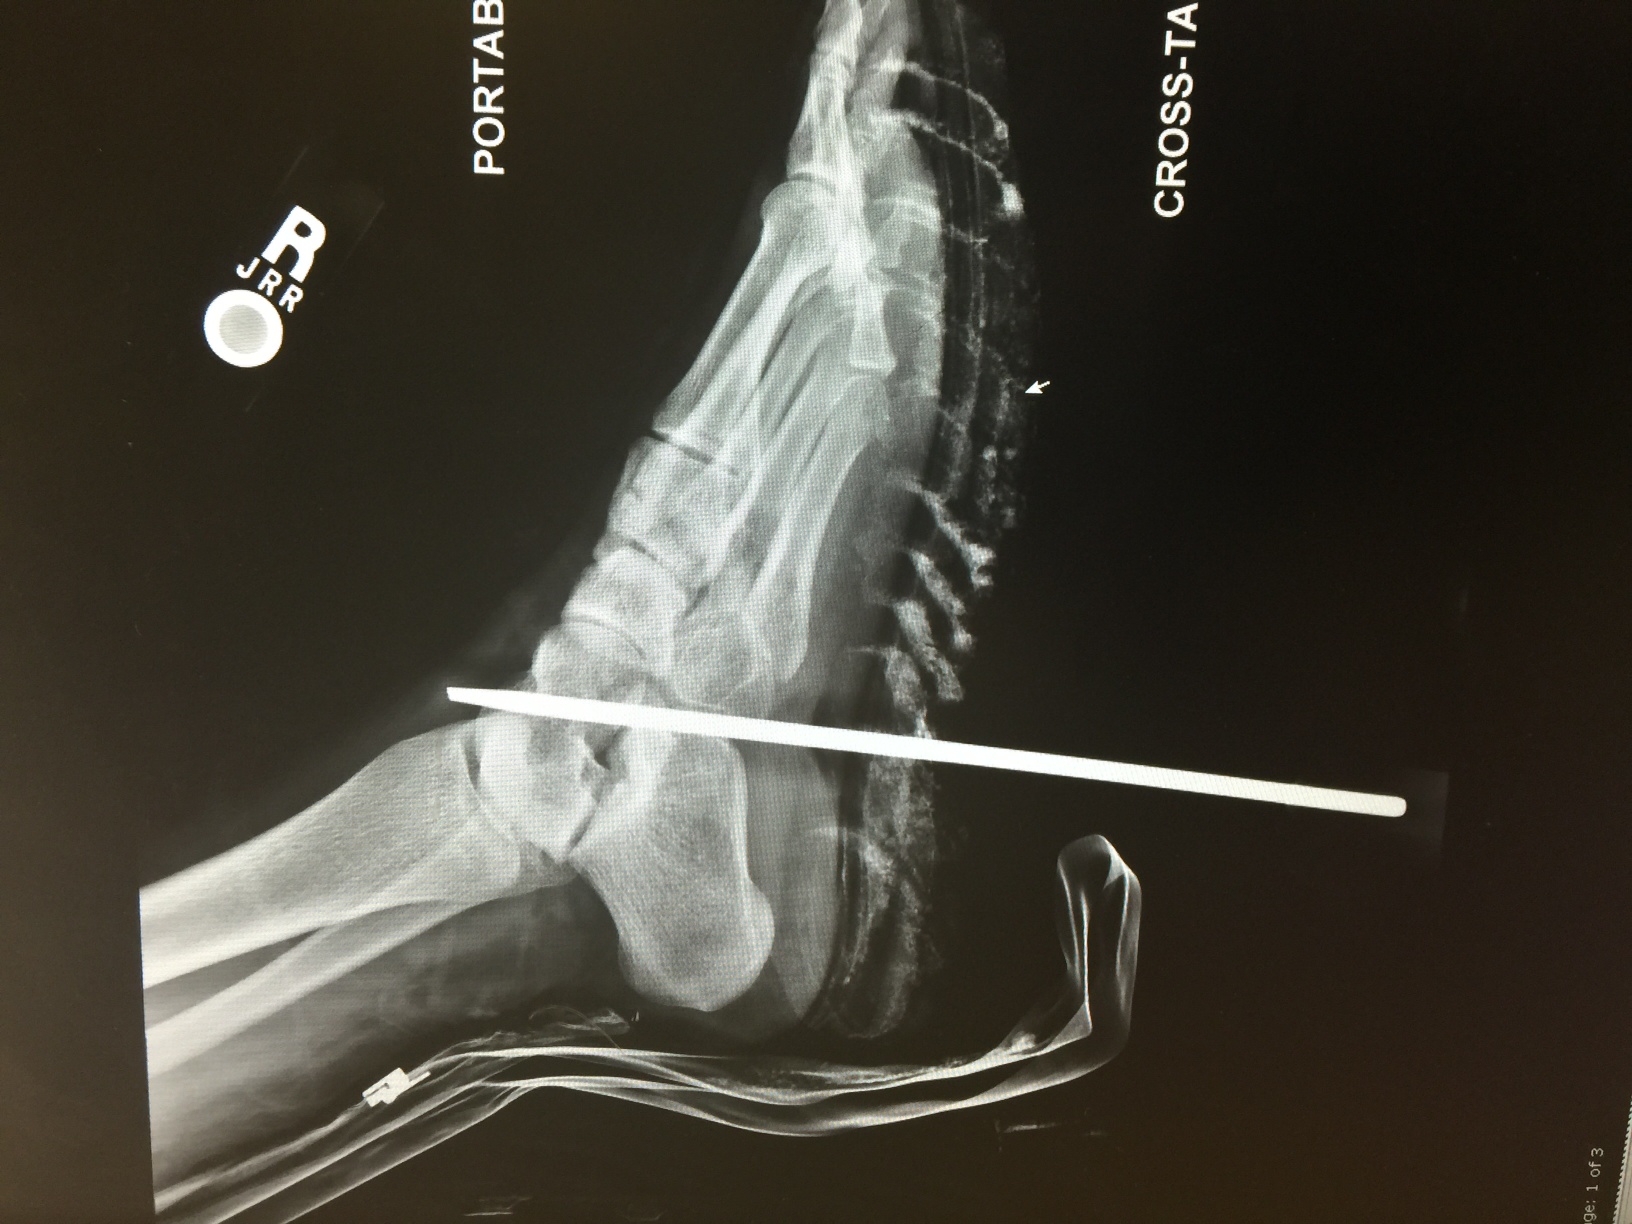

A Horrific Track and Field Accident in Texas Could be Questionable

Anxiety is severely heightened when a mother receives a phone call explaining that their son or daughter has been involved in an accident, but the accident that was explained to Sandra Seanez about her daughter, left her paralyzed and speechless. Sandra’s daughter (name not to be mentioned) had received a scholarship to play track and field at […]